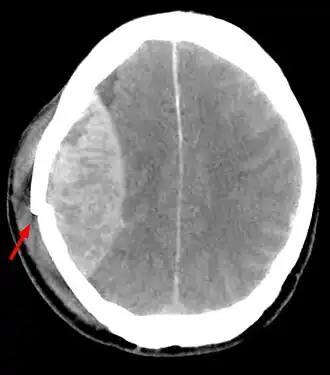

L'examen de référence réalisé en urgence devant un traumatisme crânien est une tomodensitométrie cérébrale et médullaire sans injection de produit de contraste[3] : en effet, tout traumatisé crânien est un traumatisé du rachis jusqu'à preuve radiologique du contraire.

La tomodensitométrie cérébrale sans injection de produit de contraste confirme le diagnostic et permet de noter des :

- Signes directs : hyperdensité spontanée en lentille biconvexe[2]. Elle précise les caractéristiques de l’hématome : siège, étendue, retentissement de l'hématome sur le cerveau. (effet de masse sur les ventricules) ;

- Signes indirects : refoulement d’un ventricule[2], déplacement d’un plexus choroïde, déplacement de la ligne médiane ;

- Lésions associées[2] : hypodensité piqueté de flaques hémorragique hyperdenses : attrition sous-jacente, un corps étranger.